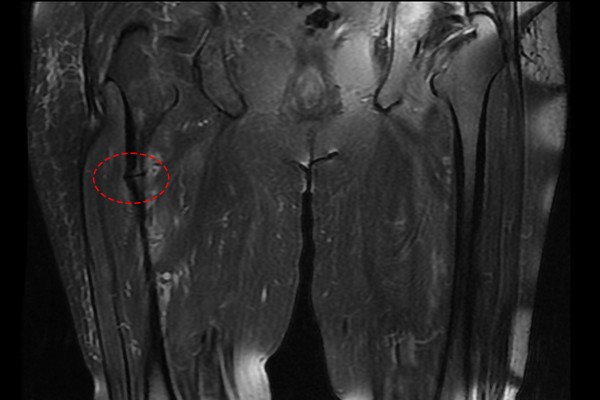

영상의학검사에 앞서 병력 청취를 하던 중 환자분께서 골다공증 주사를 3년 이상 꾸준히 맞으셨다는 것을 들었고,

X-RAY 검사를 진행하였는데, 사진 상 대퇴골 부위에 울퉁불퉁한 튀어나온 부분과 함께 금이 가있는 것을 확인하였습니다

뼈가 울퉁불퉁한 것은 뼈가 살짝 부러졌다가 붙었다 반복하면서 튀어나오고 골막이 두꺼워진 것을 뜻합니다.

MRI 검사 상에서도 골절을 확인하였고,

우측 비전형 대퇴골 전자하부골절 (Atypical Fx. subtrochanter femur Rt.)을 진단하였습니다.